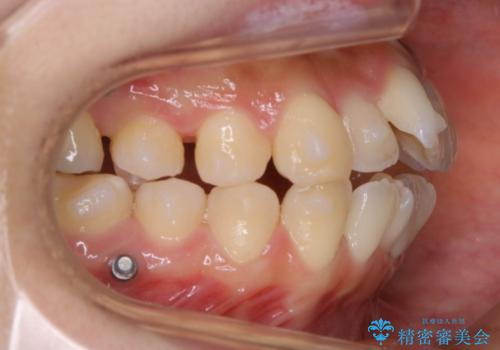

- 上下の歯のガタつきを主訴にご来院されました。

前歯部に特にガタつきが見られ、正中もズレている状態でした。

矯正装置の希望がインビザラインだったため、マイクロインプラントを併用し、奥歯から順に遠心移動をかけていくことにより非抜歯でも主訴のガタつきを治すことができました。